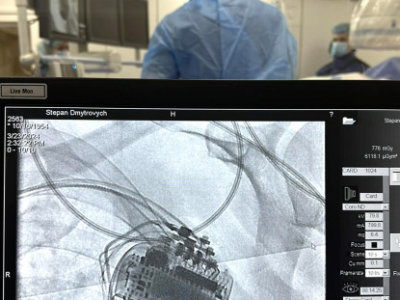

Днями у Чорткові відбулась історична подія для нашої медицини. У Чортківська центральна міська лікарня 69-річному пацієнту із Горішньої Вигнанки успішно імплантували в серце трикамерний кардіовертер-дефібрилятор. Оперативне втручання чортківські лікарі виконували спільно із фахівцями Національного інституту серцево-судинної хірургії ім. Амосова (м. Київ). Сам пристрій лікарня безкоштовно отримала від Міністерства охорони здоров’я, його вартість становить понад 300 тисяч гривень.

Пацієнту імплантували кардіовертер-дефібрилятор з метою відновлення та нормалізації порушень ритму серця, простими словами – він дозволить ослабленому серцю ритмічно битися. У пацієнтів, яким імплантували такий пристрій, навіть після перенесених інфарктів тривалість і якість життя значно поліпшується.

Операцію виконували лікар-хірург відділення лікування складних аритмій з рентгенопераційною Національного інституту серцево-судинної хірургії ім. Амосова Євген Перепека, а асистували йому фахівці Чортківської лікарні Тарас Сивак, Денис Хаблак, Марта Оробчук, Тарас Мазур, Роман Михальчук, Наталія Шишка.